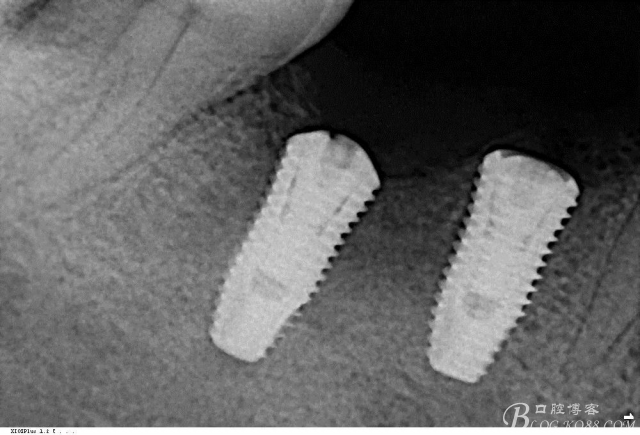

植入植體

三維檢查種植體位置,方向,平行度